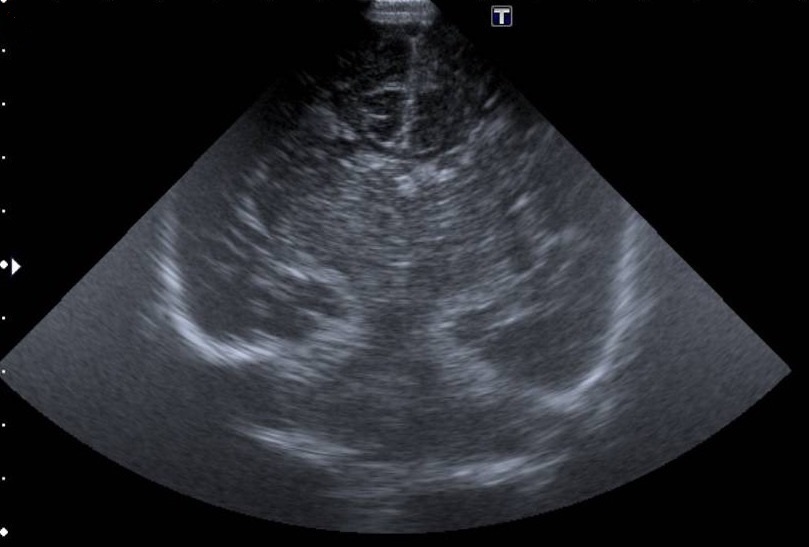

Se le realizaron radiografía de tórax, ecografía abdominal y cerebral sin hallazgos patológicos además de ecocardiografía sin cardiopatía estructural demostrable y analítica con valores dentro de la normalidad.